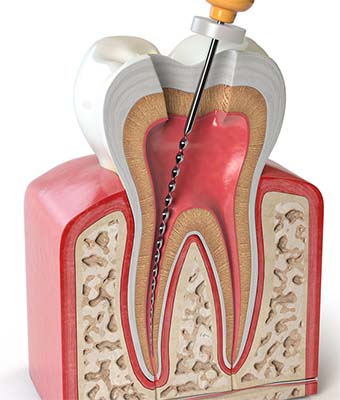

La Endodoncia es, como hemos dicho, la extirpación total de la pulpa o nervio del diente. Se trata de un procedimiento de limpieza del sistema de conductos radiculares en el que se eliminan bacterias y tejido necrótico para dejar el conducto lo más aséptico posible. Se realiza en diferentes fases:

3. Apertura de la pieza: se realiza una cavidad en la corona del diente mediante la cual se accede a la pulpa para su extracción.

4. Instrumentación: es el procedimiento de limpieza de los conductos o canales radiculares para dejarlos asépticos o limpios.

5. Obturación: es la fase de sellado de los conductos que se han limpiado previamente, utilizando pastas y cementos biocompatibles.